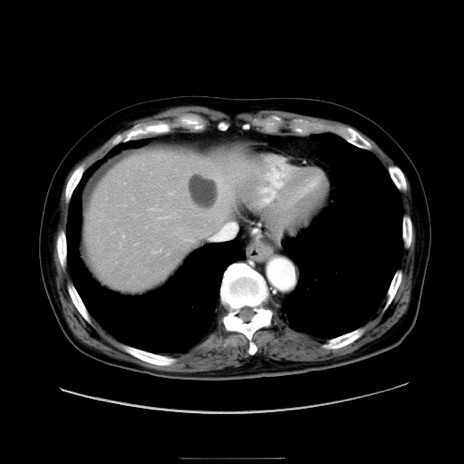

症例30(横断像)

【症例】80歳代男性

【主訴】臍周囲痛

【現病歴】約6時間前から臍下部痛が出現。次第に腹部膨隆・背部痛も生じてきたため来院。背部痛の場所は変化しない。

【身体所見】意識清明、BT 36.3℃、BP  131/87mmHg、P 87bpm、SpO2 100%(RA)、臍周囲自発痛・圧痛あり、反跳痛なし、自発痛部位に一致して板状硬あり、腹部膨隆、腸雑音減弱、CVA tenderness両側陰性。

【データ】WBC 19600、CRP 0.33